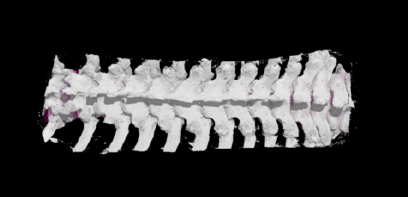

Inspiring Minds: How can we enhance anatomy education using digital technologies?

March 05, 2025

MSc candidate Sidney Wright is exploring the integration of augmented reality and digital 3D models into anatomy education to address student needs and improve learning outcomes.